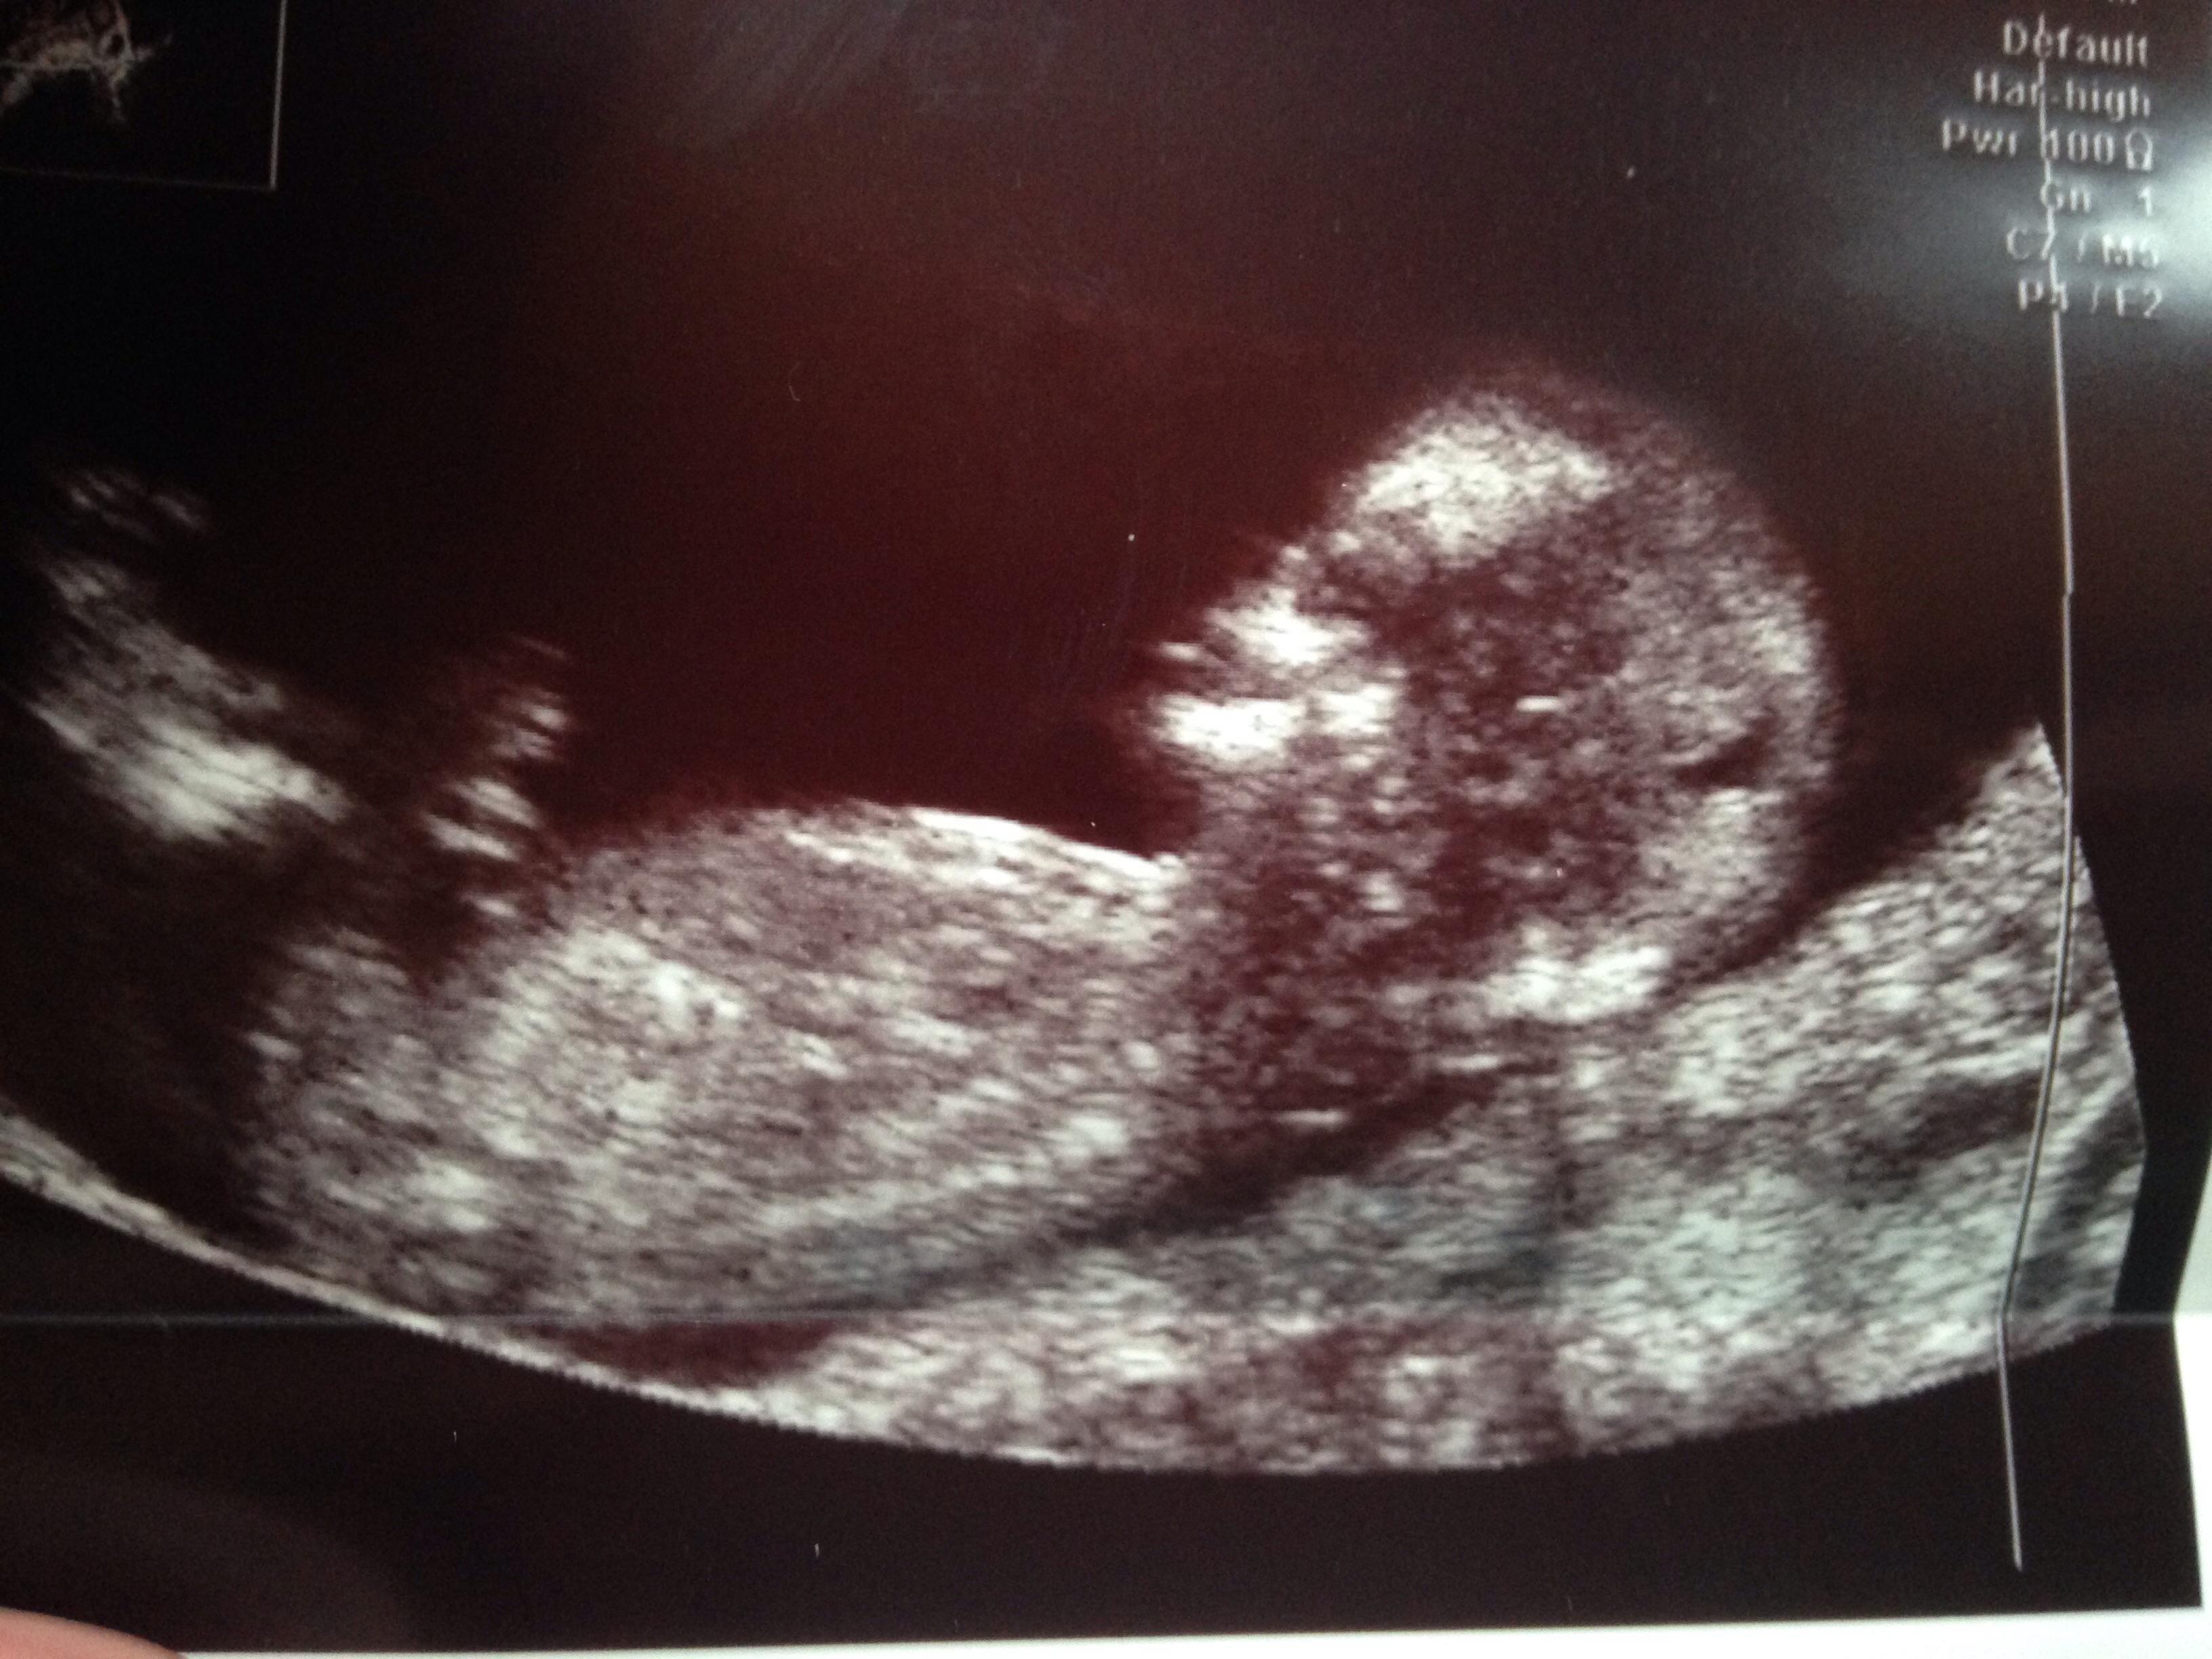

gestation is 13wks - please tell me what you all think?

I would guess boy too; the angle isn't particularly great however the nub is very obvious for 13 weeks. Good luck to her! :) xx

I thought girl from first nub pic. But last nub pic looks more angled up- boyish